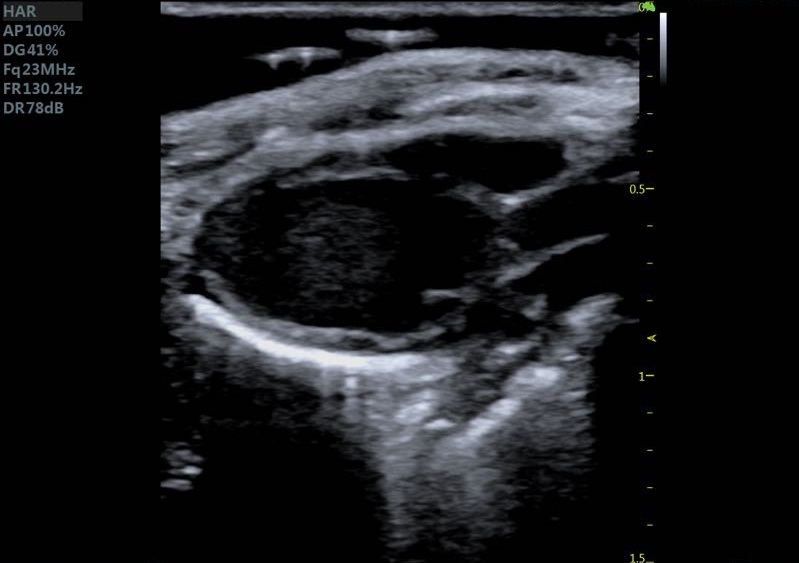

小鼠长轴B型 小鼠短轴B型

大鼠胎鼠心脏血流 大鼠心尖四腔